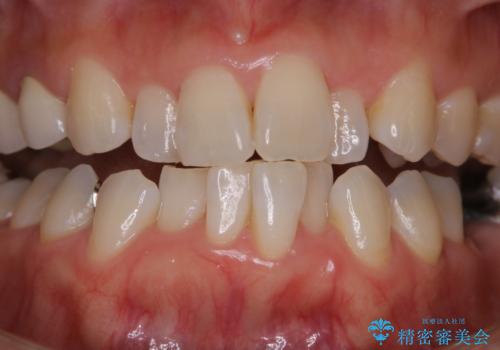

矯正治療の開始前にPMTCで汚れの除去

- これから矯正治療が開始される方です。装置の作成前にクリーニングを希望とのことでした。PMTC30分コースを行いました。

プラーク(細菌の塊)や歯石がたまると歯の表面はザラつきいてきます。そのザラつきは歯周病や虫歯菌の棲家となります。そのまま放置すると、歯肉が腫れてきたり、歯肉から出血したり、口臭が強くでたりします。とくに歯肉の境目は、歯磨きで汚れを除去することが難しく、プラーク(細菌の塊)や歯石が溜まりやすい場所です。

歯並が、がたついている場合はなおさら汚れが溜まりやすいです。矯正治療前や定期的にPMTCをすることで、矯正治療中の歯肉トラブルを防ぐことにつながります。